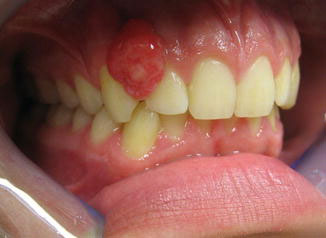

Epulis

A nonspecific word for any inflammatory cellular proliferation or a tumor‐like growth or lump of the gingiva.

A type of tumor of the gums or jaw.

An old term for a swelling of the gum. Such a swelling is usually either a reparative ‘granuloma or consists of a mass of fibrous tissue developed around ill-fitting dentures.

Epulis is a term applied to any tumour connected with the jaws.